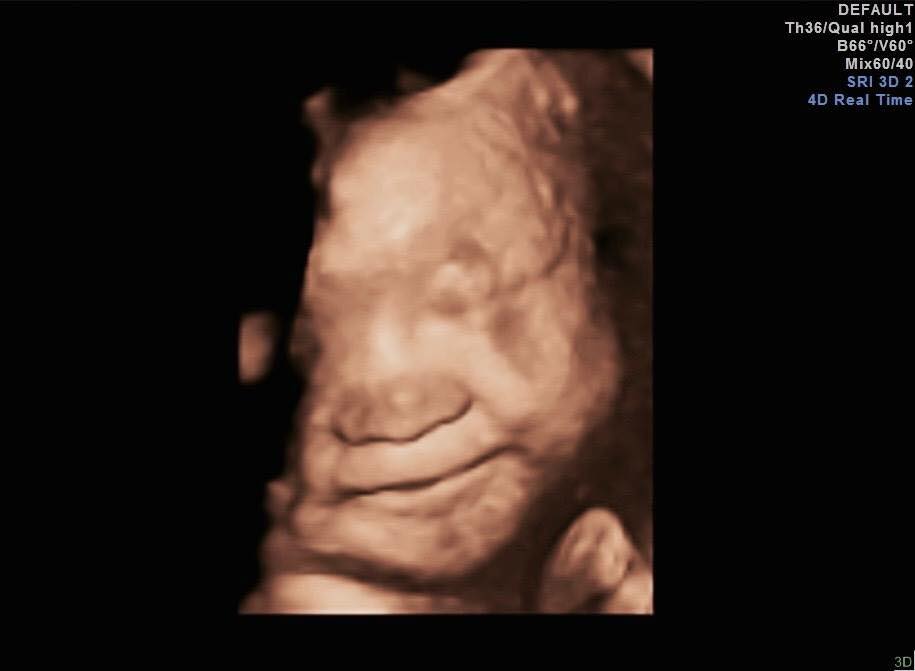

關於寶寶在肚子裡會不會有喜怒哀樂呢?

隨著超音波的進步

我們有越來越多的機會

可以看到寶寶在媽咪肚子裡有不同的表情和動作

可以皺眉頭可以打哈欠可以伸舌頭可以抓頭可以托腮可以吞嚥

當然

也可以像我放上來的這兩張照片

可以微笑